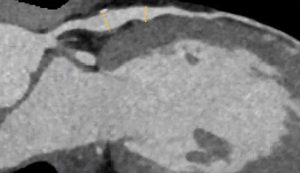

Hình. Cùng một bệnh nhân ở trên.

Hình ảnh mặt phẳng coronal cho thấy một vùng trung tâm có đậm độ thấp xung quanh lòng mạch của LAD. Vùng có đậm độ thấp này được bao quanh bởi một vùng có đậm độ cao hơn. Dấu hiệu này là dấu hiệu vòng khăn ăn (napkin-ring sign) đã thảo luận trước đó, đây là một đặc điểm mảng xơ vữa có nguy cơ cao. Bệnh nhân này được phân loại là CAD-RADS 4A/P1/HRP.

Tiếp tục với các hình ảnh tiếp theo bên dưới của cùng một bệnh nhân…

Hình ảnh chếch đôi (Double-oblique) (A) và hình ảnh tái tạo thể tích (VR) (B) của LAD cho thấy vị trí và chiều dài của mảng xơ vữa. Ngoài ra, có thể thấy tình trạng hẹp ở nhánh chéo D2 của LAD trên hình ảnh tái tạo thể tích (VR). Do mức độ hẹp và dấu hiệu vòng khăn ăn (nhìn thấy trên hình ảnh mặt phẳng axial), bệnh nhân này đã được chụp động mạch vành xâm lấn (ICA), trong đó tình trạng hẹp nặng đã được xác nhận.